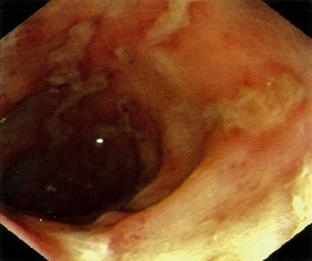

En casos de estreptococo bovis se asocia con cáncer o pólipo en el colon.

El flujo turbulento daña el endotelio de las válvulas activando la hemostasia y se forman vegetaciones asépticas formadas por plaquetas y fibrina (trombo estéril). Luego, estas se contaminan debido a una bacteriemia por un foco séptico, formándose una verruga bacteriana (vegetación séptica), la cual puede destruir la válvula (rotura de cuerdas tendinosas, músculo papilar) y formar abscesos, produciendo la clínica cardiaca; los émbolos sépticos que pasan a la circulación sistémica dan lugar a la clínica extracardiaca (en casos de ADVP, predominan los émbolos pulmonares).

La triada clínica es fiebre (95 %), soplo de regurgitación (85 %) y esplenomegalia (30 %) . Además, podría haber clínica extracardiaca producto de los émbolos sépticos al territorio de la arteria cerebral media, como hemiparesia por un ictus isquémico en pacientes jóvenes o manifestaciones embólicas pulmonares (tos, disnea y hemoptisis), que son más frecuentes en los pacientes ADVP.

Masa oscilante sugerente de verruga o absceso o dehiscencia de prótesis.